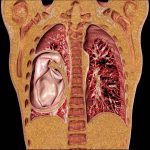

Tuyến ức còn gọi là tuyến hung nằm trước tim và giữa hai phổi. Là một mô bạch huyết, một phần của hệ miễn dịch, tuyến ức hoạt động mạnh trong 15 năm đầu của đời người, sau đó kém hoạt động và thoái hóa dần. U tuyến ức (Thymoma) là u hiếm của trung thất nhưng là u nguyên phát thường gặp nhất của trung thất trước. Điển hình gặp ở người lớn >40 tuổi, ít gặp ở trẻ em. Tiến triển chậm, xâm lấn cấu trúc lân cận, màng phổi, màng tim nhưng hiếm di căn xa…